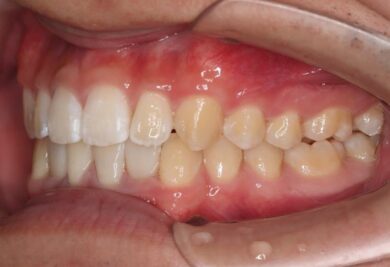

インビザラインの治療計画では、下顎前歯がより美しく審美的に並ぶよう、ご自身の歯とインプラントの歯がほぼ同じ幅径になるよう計算し配列を行いました。

インプラントは世界シェアNo,1の「ストローマン」インプラントを採用。若年者の方も安心して長期的にお使いできるよう配慮しています。

• 治療後